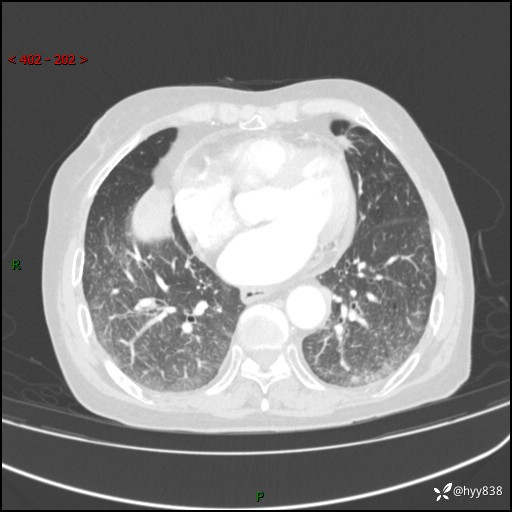

胸部CT增强(外院平扫)